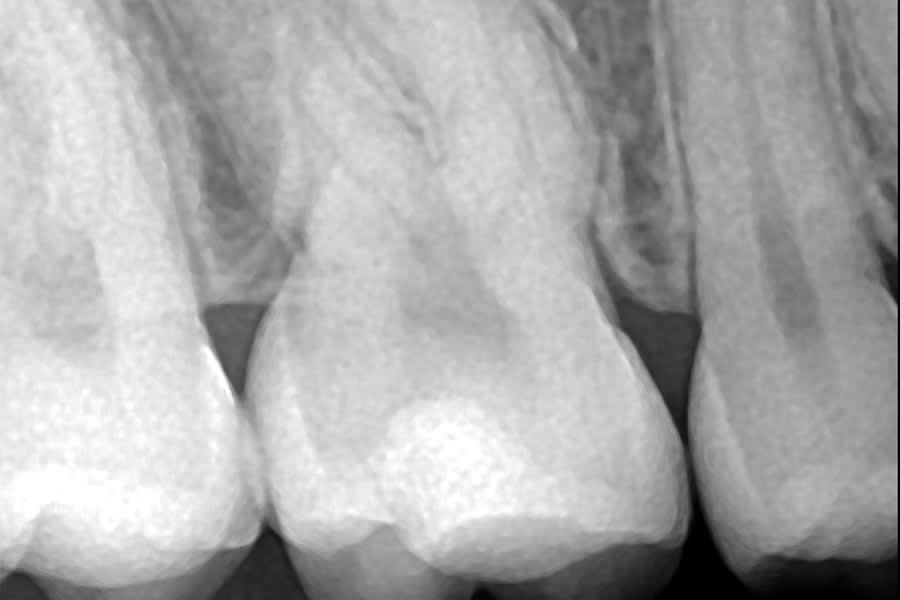

In a radiograph acquired prior to the removal of a patient's orthodontic hardware, a mid-crown radiolucency was noted on the maxillary right first molar (ie, tooth No. 3) (Figure 1). A visual examination of the crown did not indicate the presence of an obvious Class I lesion at the surface (Figure 2); however, the initial access revealed a penetrating caries lesion (Figure 3). After all of the soft carious substance was debrided, the preparation was disinfected by completing two 60-second soaks using a universal desensitizing agent with glutaraldehyde (MicroPrime™ G, Zest Dental Solutions) (Figure 4).3 Next, a round diamond bur was used to remove all of the carious dentin and establish proper retention form (Figure 5). Dentin replacement was achieved with a resin-modified calcium silicate-filled liner (TheraCal LC®, BISCO, Inc) (Figure 6). To replace the enamel, a self-etching bonding agent was applied (Adper™ Prompt™ L-Pop™, 3M) (Figure 7) followed by a bioactive resin-modified glass ionomer (RMGI) restorative material (ACTIVA™ BioACTIVE-RESTORATIVE™, PULPDENT), which was injected to overfill (Figure 8). After a curing light beam was applied for two 20-second exposures (1,200 mW/cm2) (Figure 9), a round diamond bur was used at slow speed to shape the occlusal contour (Figure 10). A final layer of the self-etching bonding agent was then applied to "glaze" the surface and improve the seal of the restoration (Figure 11), after which the occlusion was evaluated (Figure 12). The restoration was found to still be in excellent function with no signs of secondary decay or other complications at both a 2-year postoperative follow-up (Figure 13 and Figure 14) and a 5-year, 2-month postoperative follow-up (Figure 15 and Figure 16).